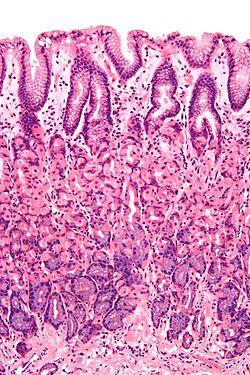

Normal gastric mucosa intermed mag.jpg

Histological section taken from the gastric antrum, showing the mucosa of the stomach